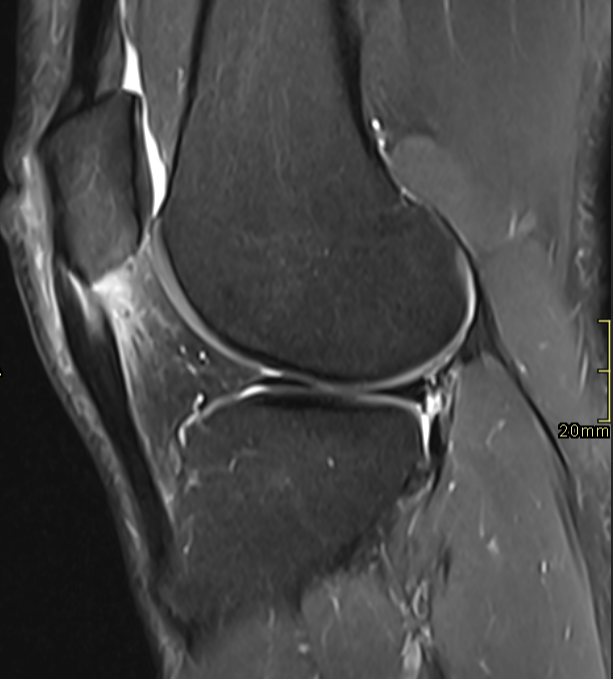

Patellar tendinosis with tear